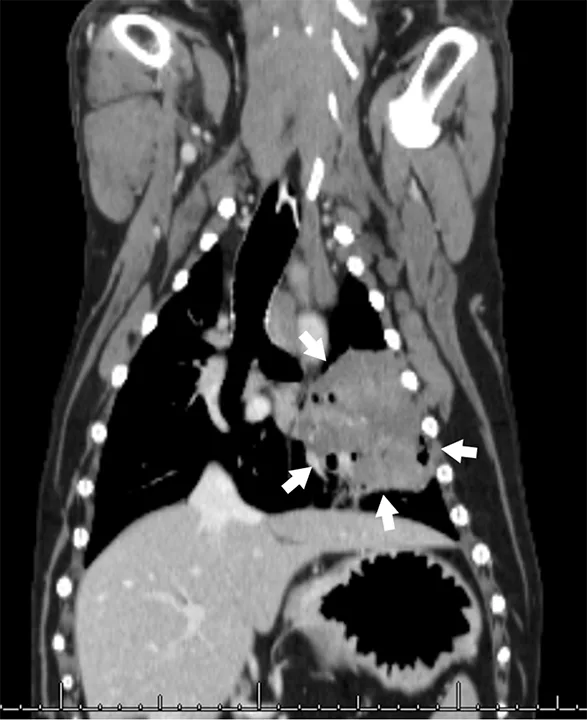

Lateral CT image of a dog with arrowheads pointing to an enlarged tracheobronchial lymph node.

FIGURE 2

Sagittal reconstruction of a CT scan (from the same patient in Figure 1) that demonstrates an enlarged tracheobronchial lymph node (arrowheads)